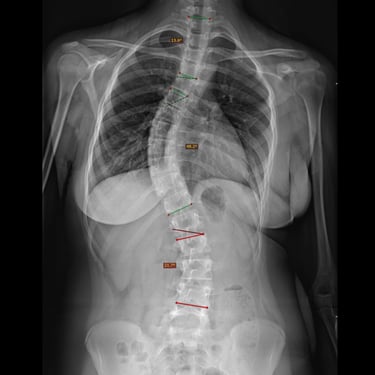

La escoliosis del adolescente idiopática del es una curvatura anormal de la columna vertebral que aparece durante el crecimiento, sin causa identificable. Su diagnóstico se realiza mediante evaluación clínica y estudios por imágenes, principalmente radiografías de columna completa, que permiten medir el ángulo de Cobb y determinar la magnitud de la desviación. En casos complejos o con sospecha de compromiso neurológico, se utiliza resonancia magnética para descartar anomalías medulares. La detección temprana es clave para definir el tratamiento adecuado —observación, uso de corsé o cirugía— y prevenir la progresión de la deformidad.